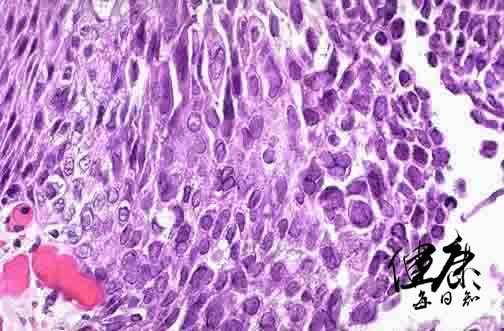

这在中医上的确会归结于上火,但是在西医临床上则认为是一种病毒。这种在嘴唇上引起水泡的病毒叫做单纯疱疹病毒HSV-1,是一种疱疹病毒!

单纯疱疹病毒HSV-1

单纯疱疹病毒他会引起多种疾病,如龈口炎、角膜结膜炎、脑炎以及生殖系统感染和新生儿的感染。是一种典型的可传染性病毒。这种病毒在感染患者后,就会感染神经细胞,一旦感染后就会出现嘴唇长水泡的症状,并且在人群中通过空气,飞沫和身体接触来传播。

单纯疱疹病毒感染患者后会释放出大量病毒,并在患者接触他人时感染到到另一个宿主的体表。这种病毒会通过表明的糖蛋白媳妇在我们健康的细胞之上,然后钻破健康的细胞膜进入内部,将自己的DNA融入细胞核,操纵细胞制造大量的病毒,最终通过宿主细胞进一步感染周围健康的细胞。

这种病毒通常最爱潜伏者我们头部的三叉神经的神经节,免疫细胞在这里权限不足,只能有限的控制病毒复制,但不能消灭它们。单纯疱疹病毒就会终生的潜伏下来,当你身体匮乏,免疫功能减退,病毒就会顺着轴突末梢直奔面部,再制造出几个水泡,传染给他人——单纯疱疹病毒引发的面部水泡是一种世界性的疾病,在我国接近1/3的成年人每年发作两次以上。在你的身上有没有发生过呢?